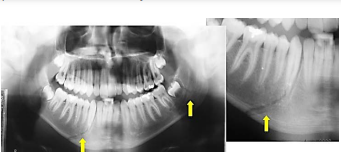

Nas áreas sinalizadas na imagem, a radiografia panorâmica evidencia traço de:

Provas

Questão presente nas seguintes provas